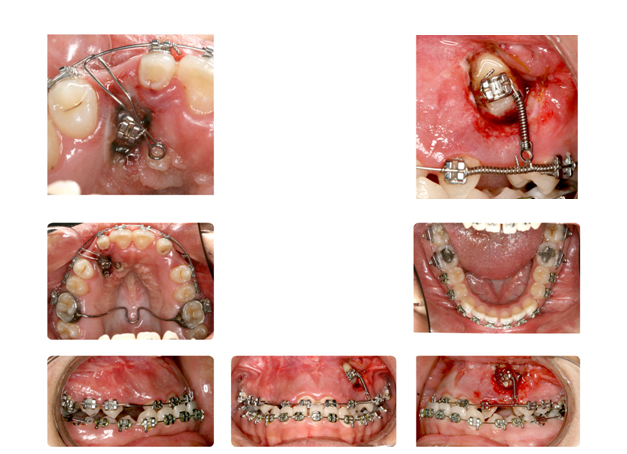

| فک پایین بیمار جلوتر از فک بالا قراردارد وهمچنین دندانهای فک بالا پشت دندانهای پایین قرار گرفته است ودندانهای نیش فک بالا بصورت نهفته می باشد: |

![]() |

| دندان نهفته ی نیش سمت راست در قسمت کام وسمت چپ در زیر لب و بالای دندانها قرار دارد که توسط جراح لثه روی آن برداشته شده وتوسط ارتودنسی و براکتها به جای برده می شود: |

| بعد از قرارگیری دندانها در جای خود ومرتب شدن آنها فک نیز آماده جراحی میباشد: |

| پس از جراحی فک وپایان درمان ارتدونسی دندانها و فک به نتیجه مطلوبی رسیده اند: |